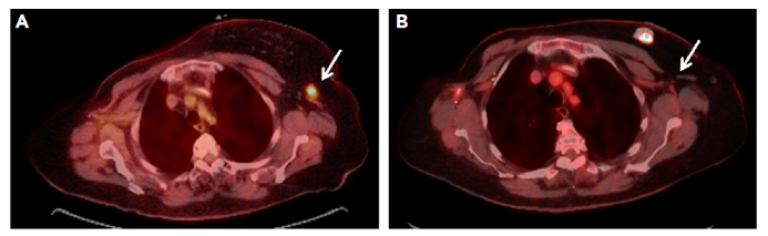

左图:2017年8月左腋下的高代谢病灶,右图为2019年8月达到CR.

患者66岁女性,右乳浸润性导管癌,ER 76%-100%,PR 10%,HER2阴性、Ki6770%。PET-CT检查未发现有明确的转移病灶。进行了术后,术后放化,采用内分泌在治疗。1年后复发。再次出现右胸壁的皮肤结节,继续接受了右胸壁的切除术,术后病理回报:浸润性导管癌,ER 76%-100%,PR 0, HER2阴性。肿瘤组织中浸润细胞TIL<2%,PDL1表达<1%。病理外,患者还进行了肿瘤组织的基因检测,结果显示:高TMB (40mut/Mb),但是没有提示dMMR。随后患者换用了氟维司群+帕博西尼方案治疗。但在治疗3个月后,患者的PET-CT检查提示疾病出现进展,左腋窝淋巴结的转移,细针穿刺提示ER 90%、PR 50%、HER2-。考虑到只是单一部位转移,患者接受了该部位的切除。切除后继续使用氟维司群+帕博西尼的治疗。继续治疗3月后,复查发现出现了右胸壁2处新的软组织的病灶复发以及淋巴结转移。患者随后在暂停了内分泌治疗,转化为每周的卡培他滨 1500mgbid口服治疗。考虑到患者肿瘤组织基因检测TMB属于高突变负荷,医生在卡培他滨治疗43天后,为患者加上了PD1单抗O药(欧狄沃,纳武利尤单抗)的治疗。患者病灶明显缩小,达到CR完全缓解转态,且到最后一次随访,26个多月后疗效仍持续。